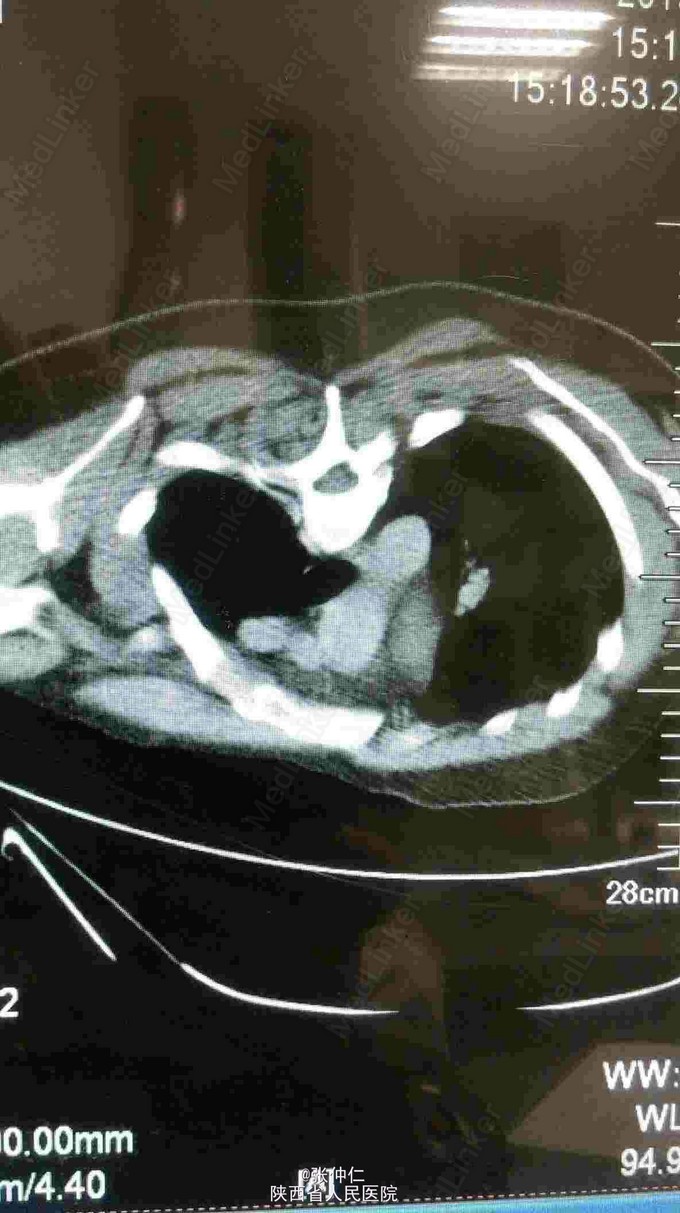

男,25岁,2年前无意间发现左腕部包块,约花生粒大,无压痛,质韧,边界清楚,搏动感明显,包块逐渐增大至板栗大小。

超声示,左桡动脉并血栓形成,门诊以桡动脉瘤收住入院。 患者神志清,精神可,二便正常,一般查体均正常。 转科查体,四肢无畸形,下肢静脉不曲张,左腕部桡侧可见大小约3*2*1.5包块,质韧,活动尚可,可触及搏动,与心脏搏动一致,皮温正常